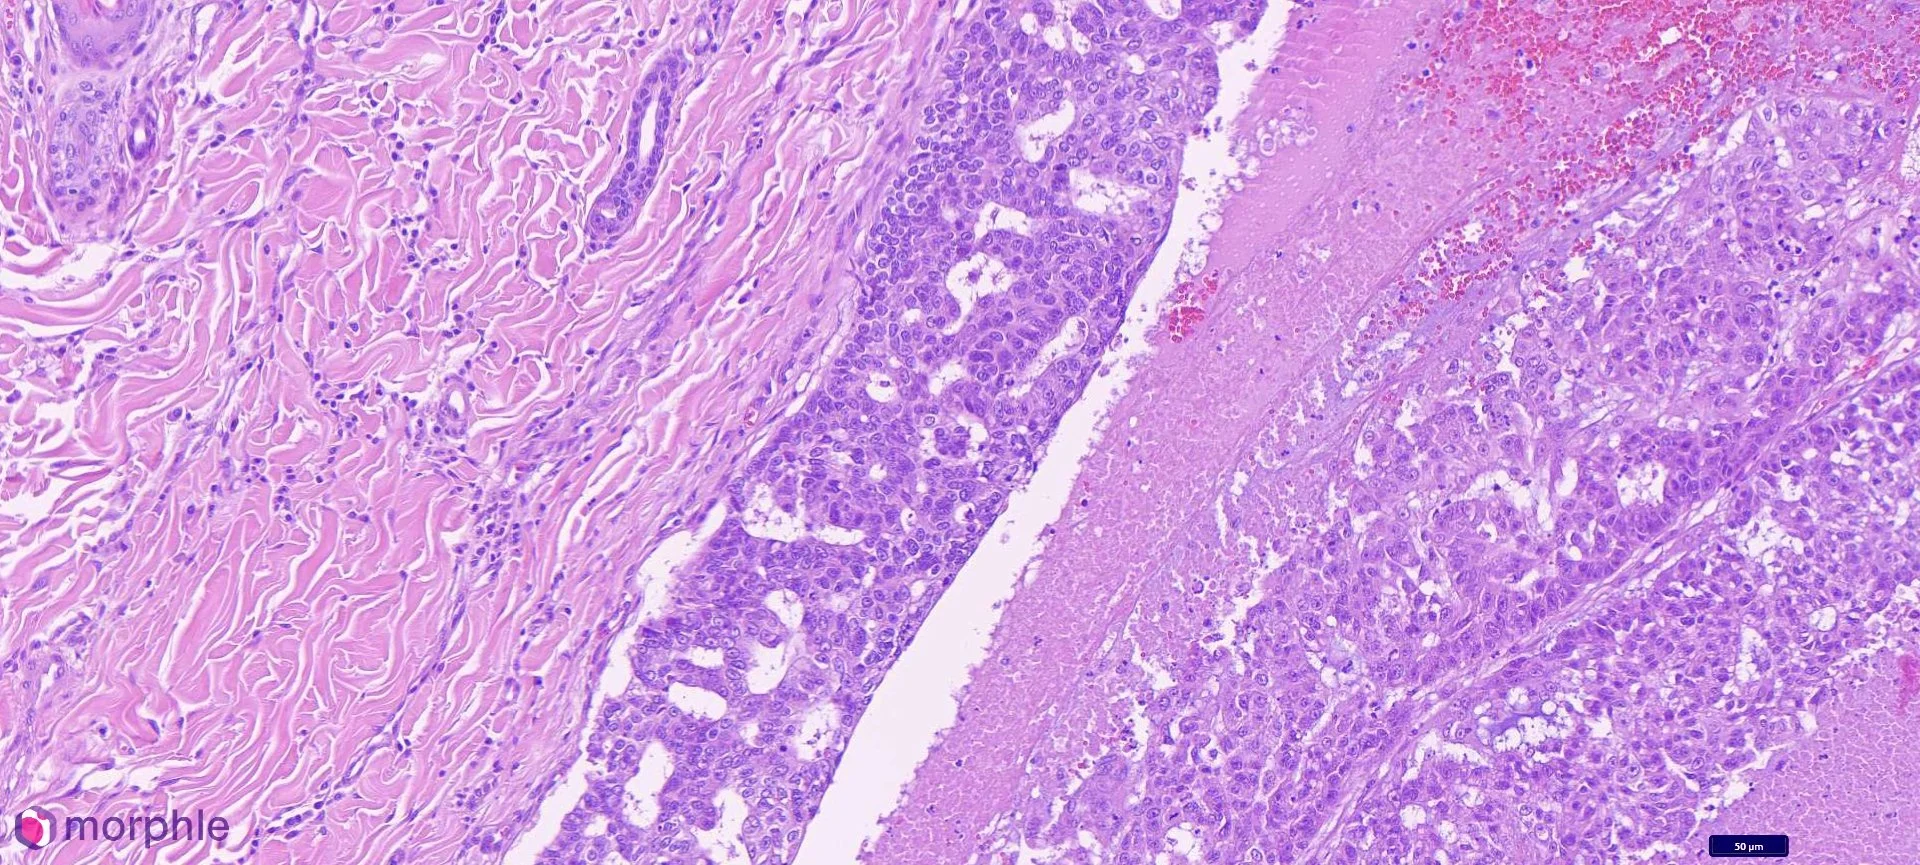

Mammary carcinoma in a male cat. This image demonstrates the edge of the neoplasm. The area to the right of center demonstrates an area of necrosis with viable epithelial cells. The area to the left is normal dermal stroma.

Sections revealed a malignant epithelial neoplasm with an infiltrative growth pattern. Neoplastic cells formed irregular tubular and solid nests separated by a moderate fibrous stroma. The infiltrative margin was a prominent feature — neoplastic cells extended into and through the surrounding soft tissue without a well-defined capsule.

The mitotic index was 11 per 2.37mm2 (not extraordinarily high); however, high enough that paired with the infiltrative growth pattern warrants a malignant diagnosis. Though, lymphovascular invasion was not identified, the neoplastic cells often encroached in vessels, which increases the suspicion for invasion in deeper sections.